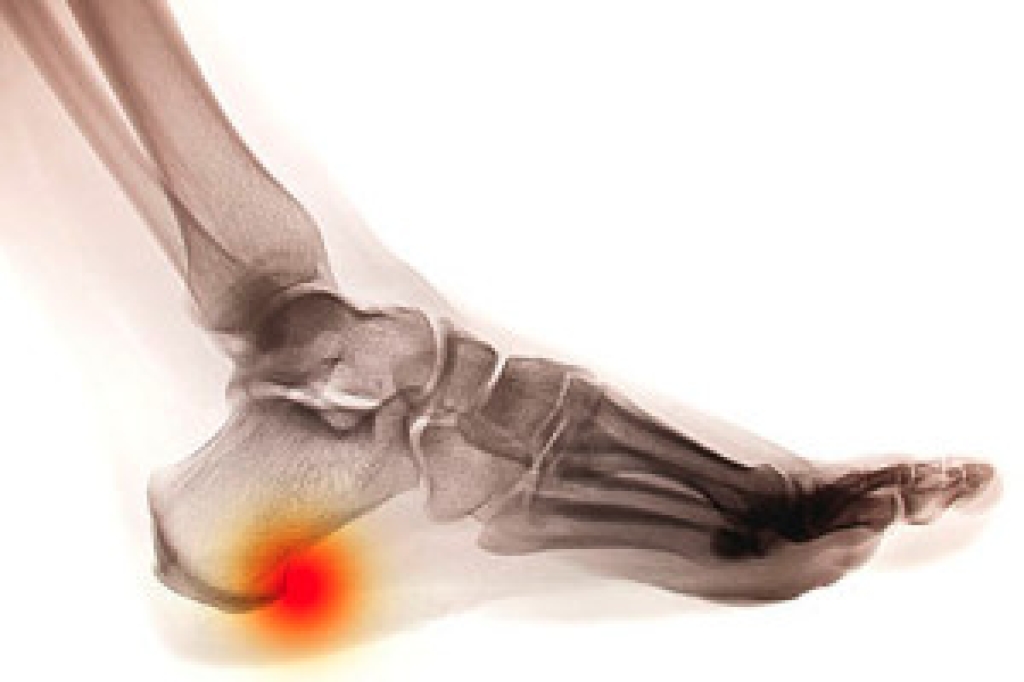

Due to the wide variety of potential causes of ankle pain, podiatrists will utilize a number of different methods to properly diagnose ankle pain. This can include asking for personal and family medical histories and of any recent injuries. Further diagnosis may include sensation tests, a physical examination, and potentially x-rays or other imaging tests.